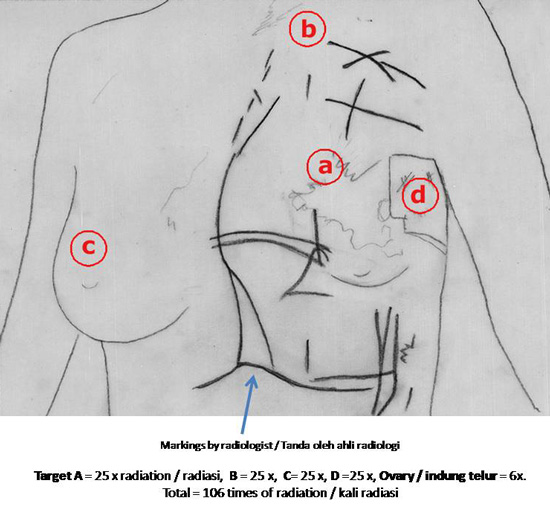

You did radiotherapy – how many times of radiation did they give you? Le: One hundred and six.

Are you sure? Is that correct? Le: Sure, correct. I received 25 treatments on my left breast (a), then another 25 times below my collarbone (b). Another lump appeared on my right breast and I again had 25 treatments for my right breast (c). Then they radiated my ovaries – that was done for six times. The cancer spread again to my left breast and I again had 25 treatments (d). Actually I have just completed the 106th treatment a few days ago. Then I came here.

You got one treatment a day, so this means you have been going to the hospitals for at least 106 times then? Le: Yes.